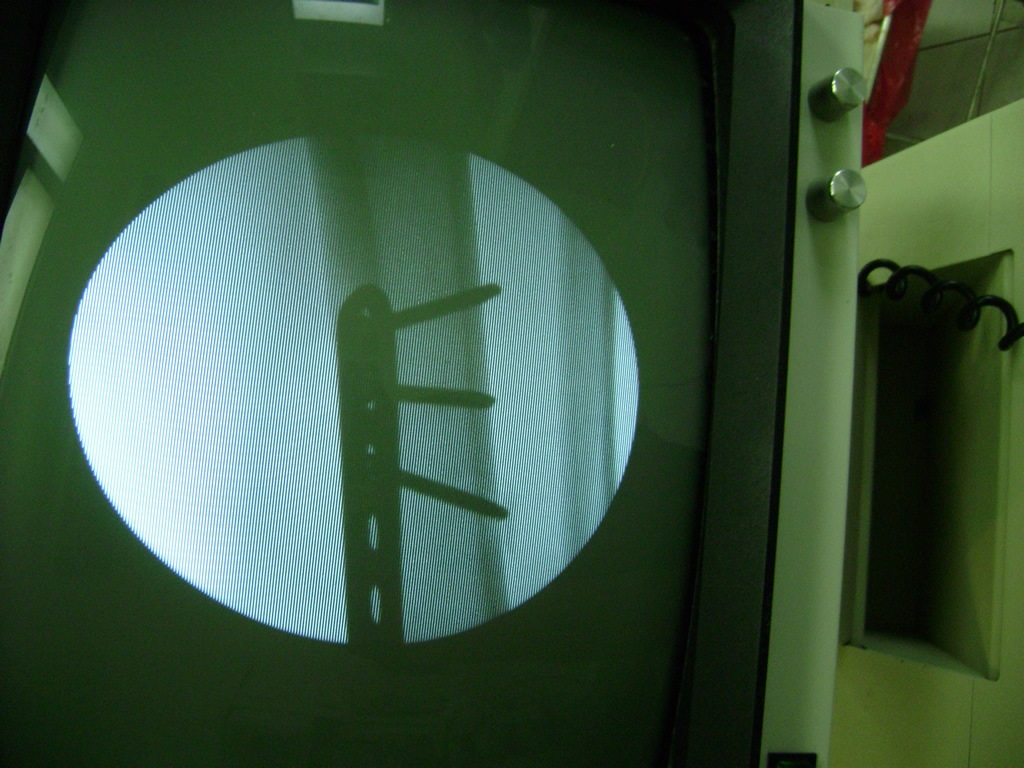

La mayor parte de las roturas implican a la parte proximal del hueso (parte del hueso próximo a la rodilla) o a la parte distal (parte del hueso cerca del tobillo).